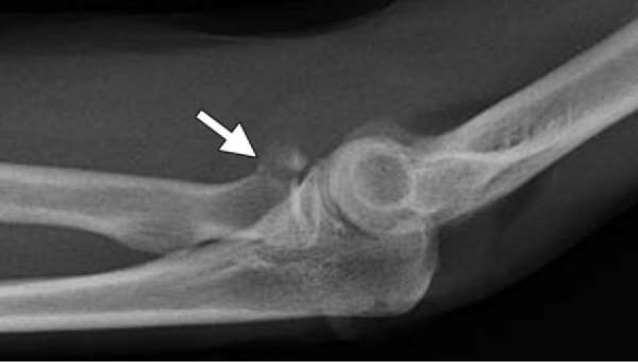

Some undisplaced radial head/neck fractures may not show up on X-ray except for which sign?

Fat pad sign

(usually seen on the lateral X-ray)